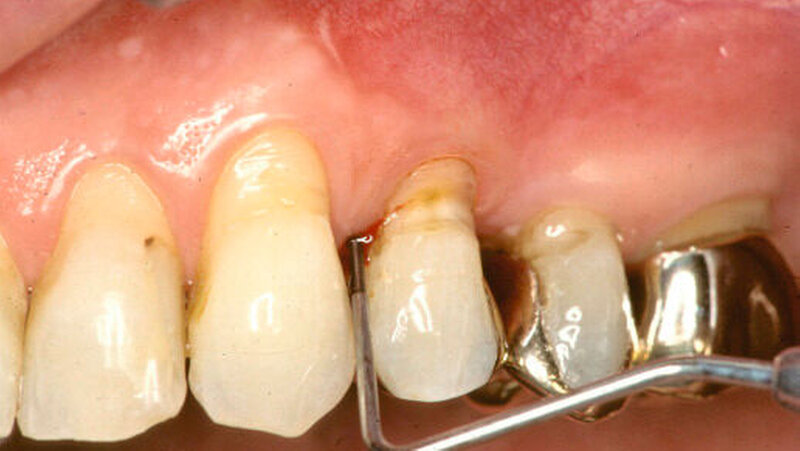

28 gesunde Studenten der Universität Campinas (Brasilien), unter ihnen 14 Nichtraucher und 14 Raucher, nahmen zwischen Juni und September 2012 an der Untersuchung teil. Zu Beginn wurden bei allen Teilnehmern der Plaqueindex, der gingivale Blutungsindex, die Tiefe der Zahnfleischtaschen, epitheliale Haftung und Neigung zur Sondierungsblutung ermittelt.

Abdrücke wurden genommen, um Acrylstents zu präparieren, die einen Bereich von einem unteren mittleren Schneidezahn bis zum zweiten Molaren mit 2 mm des Zahnfleischrandes überdeckten, die beim Zähneputzen getragen werden sollten. Die Probanden erhielten Instruktionen sowie eine Zahnbürste und -pasta für die tägliche Mundpflege. Diese sollte den normalen Gewohnheiten entsprechend durchgeführt werden, allerdings sollte keine Reinigung der Zahnzwischenräume erfolgen sowie kein Mundwasser und kein Kaugummi angewendet werden.

Zu Beginn sowie 14 und 28 Tage nach Induktion der Gingivitis wurden Proben der Zahnbeläge und nach 0, 14, 21 und 28 Tagen Proben von Sulkusflüssigkeit genommen. Aus diesen Proben wurden Daten zur Zusammensetzung der Oralflora gewonnen und Cytokinprofile bestimmt. Zudem wurden eine Woche vor Beginn sowie am Tag 0 und 21 der sichtbare Plaqueindex (VPI) und der gingivale Blutungsindex (GBI) ermittelt.